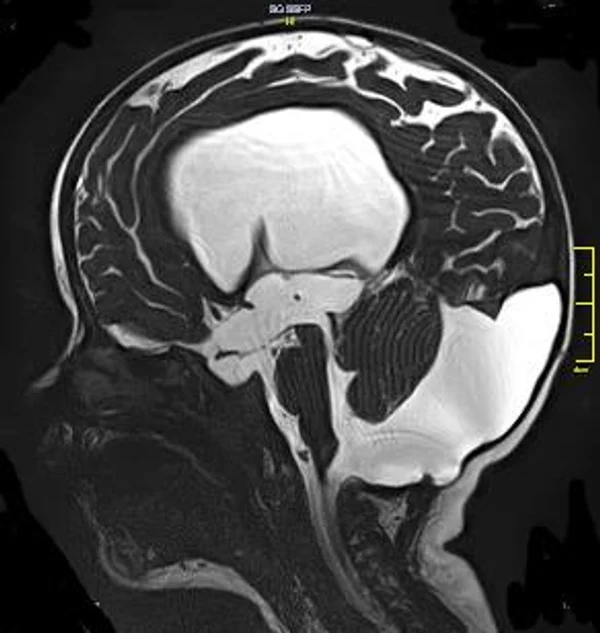

кисты, аномалии Денди-Уокера и др.Операции при внутричерепных кистах. В основном встречаются арахноидальные кисты различных локализаций и кисты сосудистых сплетений боковых желудочков. Пациентам с врождёнными кистами операции проводятся в следующих ситуациях: увеличении объема кисты в динамике, наличии клинических проявлений, компрессии и дислокации мозговых структур, наличии окклюзии ликворных путей. Нами используются 2 способа хирургического лечения кист: эндоскопическая перфорация стенок кист и открытая резекция кист. Открытая резекция кист проводится при ретроцеребеллярных арахноидальных кистах (рис. 2), при арахноидальных кистах межполушарной щели при отсутствии непосредственного контакта их стенок со стенками расширенных желудочков головного мозга и повторного увеличения кист средней черепной ямки после эндоскопической кисто-цистерностомии. Техника операции заключается в проведение краниотомии и максимальном иссечении стенок кист с созданием широкого сообщения кист с субарахноидальным пространством. Эндоскопические операции проводятся при арахноидальных кистах межножковой и пинеальной цистерн, арахноидальных кистах межполушарной щели при тесном контакте их стенок со стенками расширенной желудочковой системы (рис. 3), первично при арахноидальных кистах средней черепной ямки, а также при кистах сосудистых сплетений боковых желудочков. При арахноидальных кистах межножковой цистерны эндоскопически проводится перфорация стенок кисты, сообщая ее с просветом III желудочка и межножковой цистерной – эндоскопическая вентрикуло-кисто-цистерностомия (рис. 4). При арахноидальных кистах пинеальной цистерны проводится перфорация кисты в передне-верхних её отделах с созданием сообщения полости кисты с просветом III желудочка – эндоскопическая кисто-вентрикулостомия. С целью предотвращения облитерации сформированного отверстия иногда в полость кисты под контролем эндоскопа вводится стент перфорированный на протяжении (рис. 5, 6). Эндоскопическая кисто-цистерностомия выполняется при арахноидальных кистах средней черепной ямки. При этом создается широкое сообщение кисты с базальными цистернами. При кистах сосудистых сплетений боковых желудочков проводится их вскрытие в просвет боковых желудочков – эндоскопическая кисто-вентрикулостомия. При множественных кистах проводится их хирургическое сообщение между собой – интеркистосмия